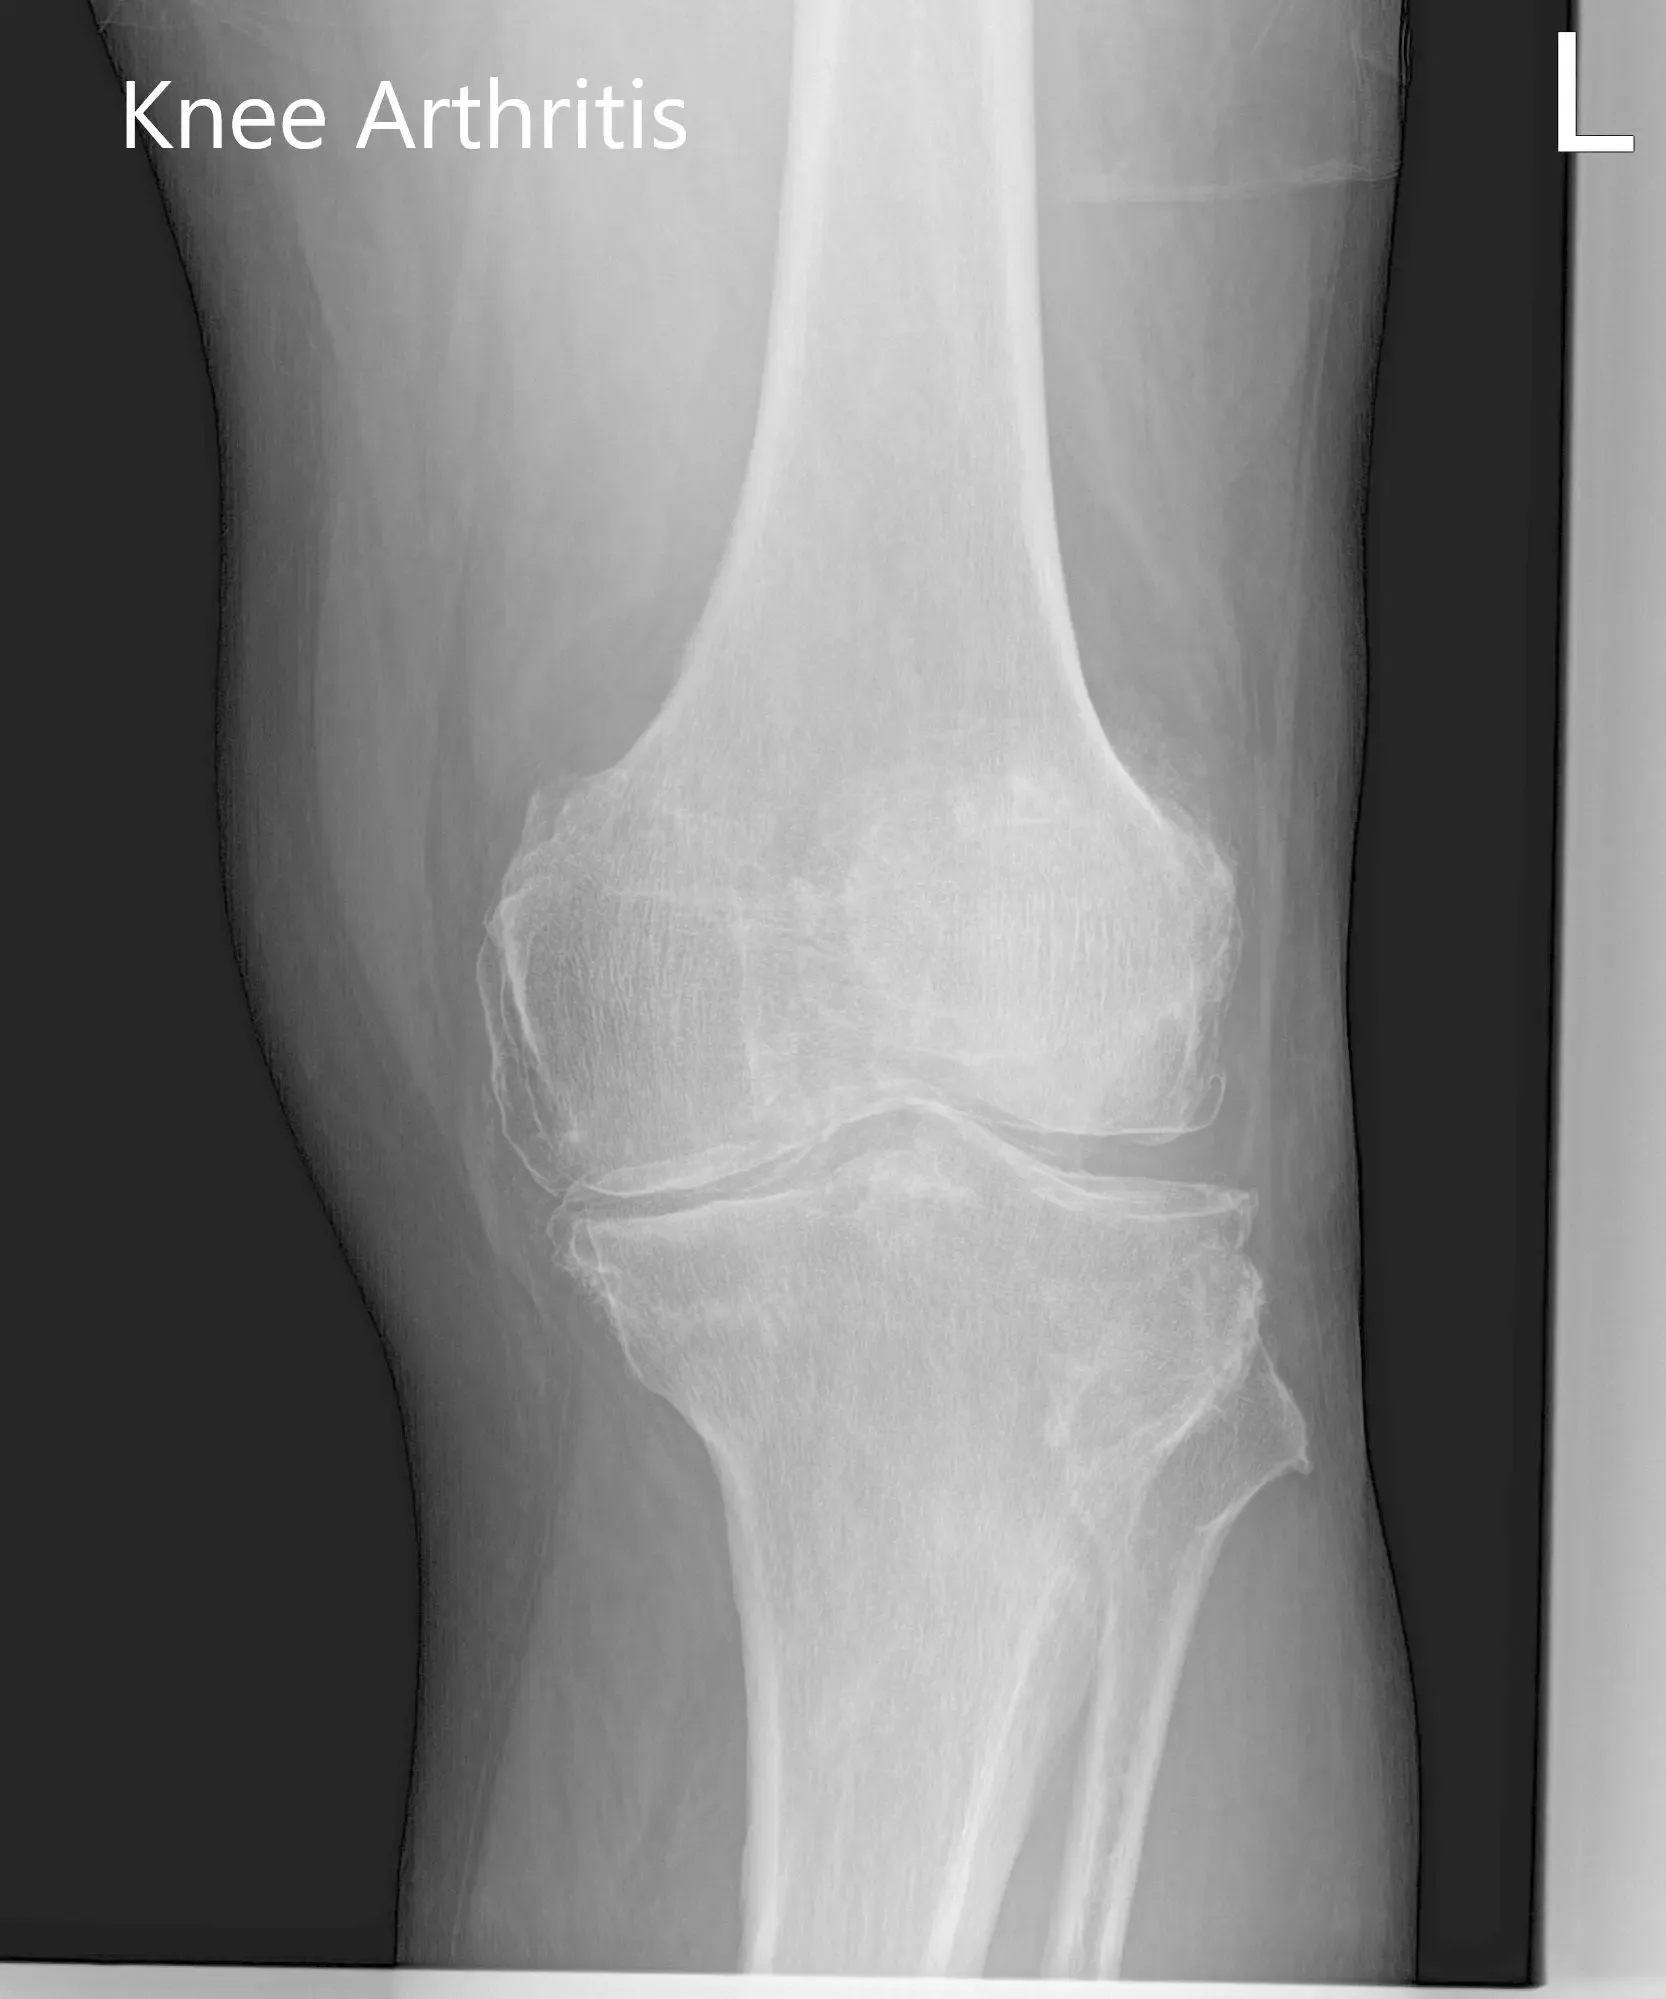

Considering his lifestyle limiting knee pain, various management options including both surgical and nonsurgical were discussed with him at length. He was considered a candidate for custom left knee total replacement. Risks, benefits and potential complications were discussed with him in detail. He agreed to the plan. Imaging studies revealed severe tricompartmental osteoarthritis of the left knee joint.

Preoperative X-ray of the left knee showing AP and lateral view of the knee with a skyline view of the patella.